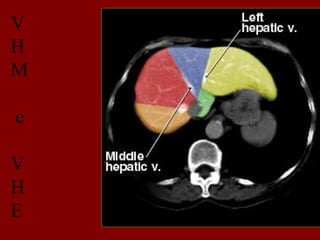

V

H

M

e

D

INCISÃO SOBRA AVEIA HEPÁTICA DIREITA

INCISÃO SOBRE AVEIA HEPÁTICA MÉDIA.

INCISÃO SOBRE AVEIA HEPÁTICA ESQUERDA.